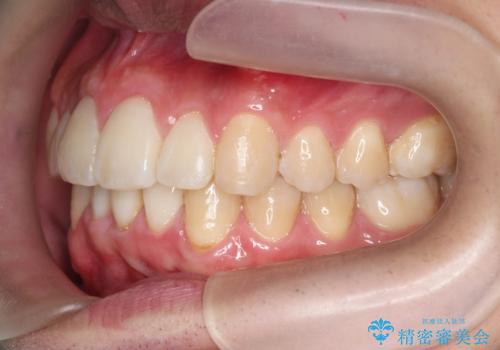

マウスピース矯正で前歯の角度、ガタガタをきれいに

- 突き出た前歯の角度、歯ブラシのしづらい前歯のがたつきの改善を希望され来院されました。

4本の小臼歯を抜きワイヤー矯正治療、下顎前歯を1本抜去しマウスピース治療のメリットデメリットを検討・相談し、より歯を抜く本数の少ないマウスピース矯正を行うこととなりました。

下顎の前歯は1本だけ抜去せざるをえませんでしたが、4本の小臼歯抜去とマルチブラケット矯正を回避することができ、治療結果・過程に満足いただくことができました。